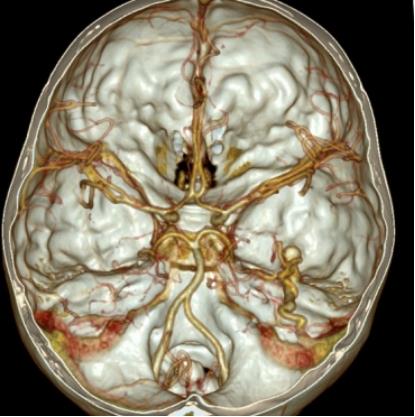

“医生、医生,快看看,我娃儿既没有摔斗,又没有碰斗的,咋子突然的喊脑壳痛,还吐了安?”在自贡市第四人民医院神经外科,一位七岁男孩的家长焦急的询问着。头颅CT发现,这位小朋友是右颞叶脑出血,破溃入蛛网膜下腔。那正如这位家长所说,这个娃娃既然没有磕着碰着,怎么会有脑出血?进一步行头颅CTA检查(一种无创的CT脑血管造影检查),发现右颞一动静脉畸形,原来引起儿童出血的罪魁祸首是---脑动静脉畸形。

术前CTA